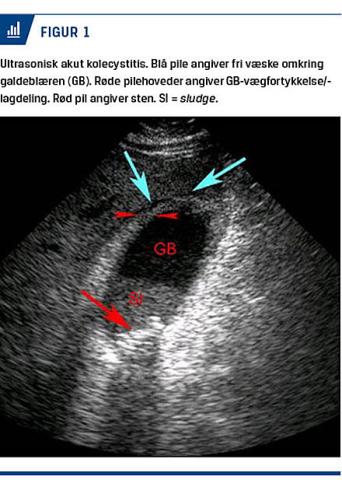

UL-skanning af abdomen er den primære billeddiagnostiske undersøgelse til diagnostik af AC [9]. Undersøgelsen er noninvasiv, hurtig at gennemføre og meget velegnet som førstevalgsundersøgelse. De vigtigste ultrasoniske fund er, fraset konkrementer, lagdeling af GB-væggen, GB-vægfortykkelse (≥ 5 mm), væske omkring GB [10] (Figur 1) samt en hyperæmisk væg ved undersøgelse med farve-Doppler [11]. UL-skanning har en sensitivitet på 81% og en specificitet på 83% for evaluering af patienter, hos hvem der er mistanke om AC [12], men det er ofte vanskeligt at påvise sten i de dybe galdeveje [8]. UL-visualisering af GB-sten har

en positiv prædiktiv værdi i kombination med positivt Murphys tegn på 92% og med GB-vægfortykkelse samt lagdeling af GB-væggen på 95% for diagnostik af AC [13]. Sensitivitet for diagnosticering af GB-perforation som komplikation i forbindelse med AC er nedsat og kan tilskrives faktorer som overvægt, akustisk skygge fra sten og artefakter pga. pneumobilia [14, 15].